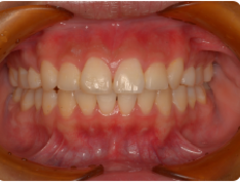

「上の前歯のデコボコを治したい」このような相談は、非常に多いです。

マウスピースで簡単に治せます。他院だと相場で1個につき20,000円前後。

当院は1個につき5,000円です。